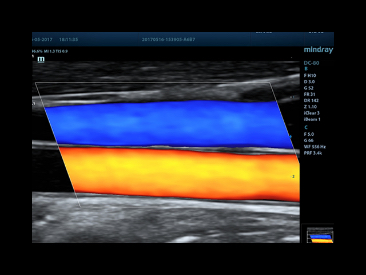

Smart Track

ItŌĆÖs Mindray unique feature to reduce repetitive, time-consuming scanning steps in vascular exams. Smart Track provides intelligent and real-time vessel tracking and real-time image optimization of Color and PW.